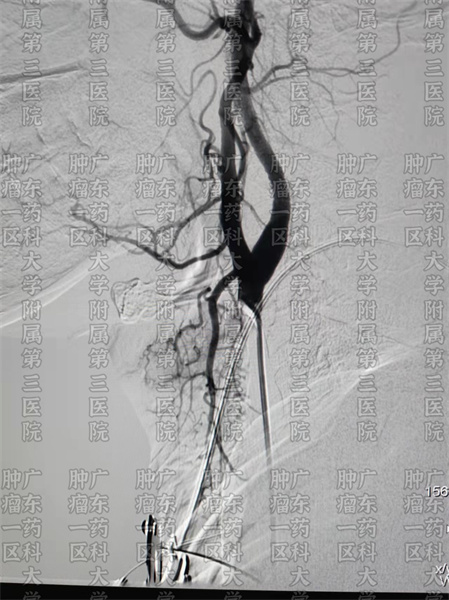

尽早确证,也能今早为患者进行对症治疗。那么喉癌有治疗方案吗?有什么治疗方案?喉癌的预后如何呢?广药三院肿瘤科一区针对喉癌的治疗,目前包括微创动脉灌注治疗,微创动脉栓塞治疗,生物治疗等。

彭齐荣主任、张涛医生团队会为喉癌患者进行多学科会诊。根据不同的患者,采用不同的治疗方案,有时是多种方式联合治疗,有时是微创结合中医药等全身治疗。医生指出,想要喉癌患者获得更好的疗效,除了要尽早发现,积极治疗以外,找到合适自己的治疗方案非常重要。

在广药三院肿瘤科一区,医生会根据患者不同的原发部位、不同病期,结合患者的全身情况采取不同的治疗手段。发挥微创技术副作用低,创伤小的优势特点,在尽可能大限度地去根 . 治肿瘤,同时减轻患者的负担,提高患者生活质量。尽可能保留喉功能的目的,让喉癌患者术后的生存期和社交、生活等生存质量尽可能恢复正常。